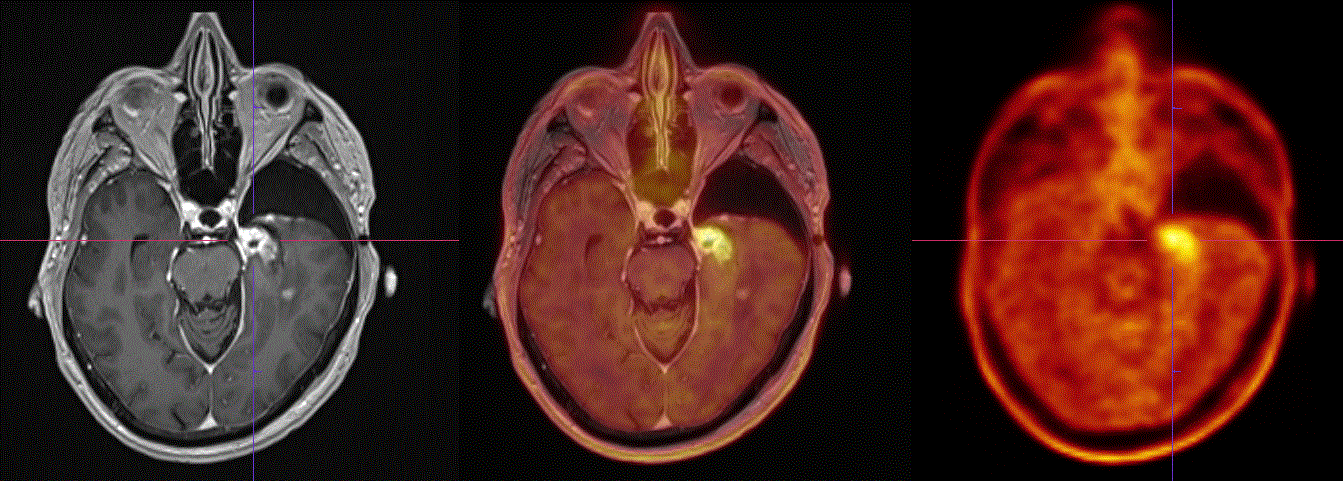

Ukázka vyšetření

Na obrázku vlevo zobrazuje T1 sekvence MR ložisko za postresekční dutinou mediotemporálně vlevo se zvýšeným sycením MR kontrastní látkou. Na obrázku vpravo je ve zmiňovaném ložisku patrna intenzivní akumulace FDOPA. Uprostřed je fúze obou obrazů PET/MR. S vysokou pravděpodobností se jedná o recidivu glioblastomu 17 měsíců po makroskopicky radikálním jeho odstranění a následné konkomitantní chemoradioterapii.